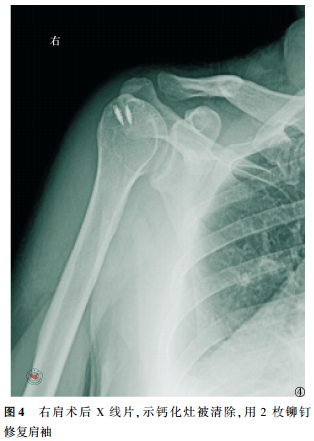

所有病例术后疼痛即刻消失,当晚夜眠良好。经过3~12个月的随访,UCLA评分由术前的(12.5±2.5)分提高至末次随访的(35.2±4.0)分,术前与末次随访比较,差异有统计学意义(t=5.317,P<0.05)。X线检查显示未见模糊的沉积病灶恢复清楚的边缘(图4);无1例发生肩关节僵硬、肩袖撕裂或新的钙化灶。

典型病例 女性患者,49岁,因“右肩关节疼痛、活动受限5d”入院,查体见右肩关节局部压痛,以冈上肌处明显,右肩关节主动活动范围受限,被动活动范围基本正常,Neer撞击征(+),术前X线片示右肩峰下一巨大密度增高团块(图1),磁共振示右冈上肌腱内一信号增高团块(图2),诊断考虑“右肩关节钙化性肌腱炎”,行“右肩关节关节镜探查清理+冈上肌腱钙化灶清理+肩袖修补术”,术中清理右肩冈上肌腱内牙膏样的乳白色稠状物,即钙质沉积(图3),见肌腱裂口超过肩袖厚度的1/2,予2枚铆钉修补肩袖,术后复查右肩关节X片(图4)。术后患者疼痛程度明显减轻,随访9个月,UCLA评分由术前的11畅5分提高至33畅5分,且无出现术后并发症。